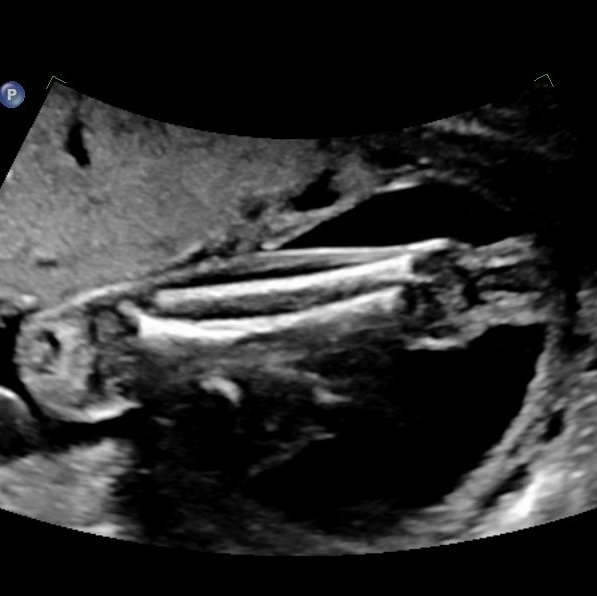

Bildtitel

Schien- und Wadenbein